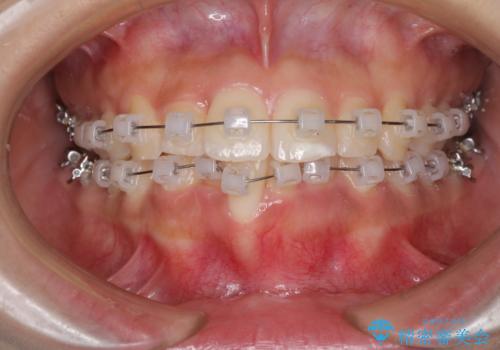

- クリアブラケット

- 治療期間

- 9ヶ月